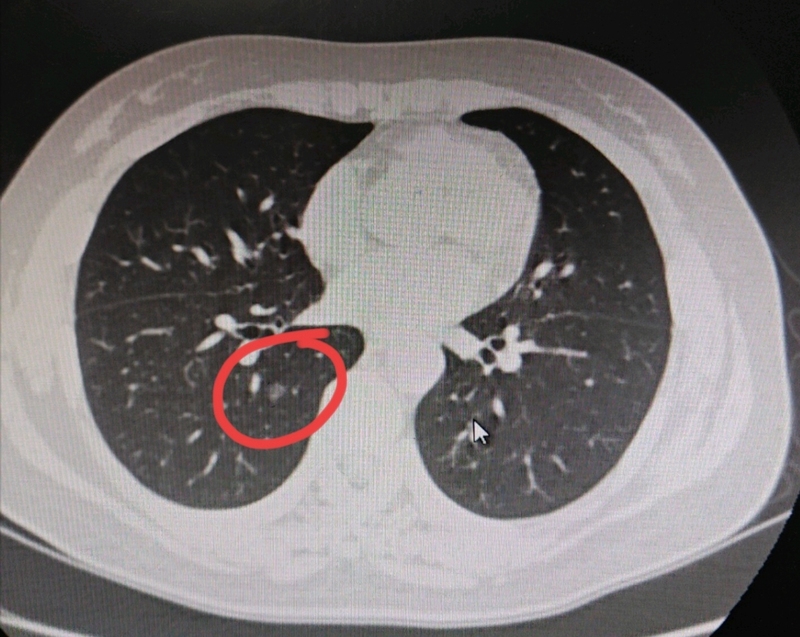

(一)话题引出的原因今天早上刷到一篇文章,主要内容如下:2025年发表于《Laradiologiamedica》的一项研究,首次系统评估了CT引导下经皮MWA治疗VATS术后残留GGN型肺癌的可行性、安全性和初步疗效。该研究纳入了来自5家医院的216例患者,共216个残留GGN病灶,接受了235次MWA治疗。文章说该研究的亮点:技术成功率100%:所有病灶均在首次消融后完全覆盖。安全性良好:无手术相关死亡。最常见并发症为气胸(31.5%),但仅12.3%需胸腔引流;其他如胸腔积液、肺部感染等发生率较低。肺功能影响小:术后1–3个月肺功能指标与术前相比无显著差异,说明MWA是一种肺组织保留性治疗。疗效显著:初次完全消融率:94.9%(205/216)二次消融后完全消融率:100%3年无局部进展生存率(LPFS):96.3%5年总生存率(OS):96.3%5年癌症特异性生存率(CSS):100%研究中纳入的患者需满足以下条件:VATS术后病理证实为I–IIA期肺腺癌;残留GGN为纯磨玻璃或混合型,实性成分≤50%,直径8–30mm;位于肺外周;年龄18–80岁,身体状况可耐受穿刺。看了这样的研究文章,是不是非常心动?肺结节患者怕开刀,终于又迎来消融与手术效果相当,而且3年无局部进展生存率(LPFS)96.3%;5年总生存率(OS)96.3%;5年癌症特异性生存率(CSS)100%。此后完全可以针对磨玻璃结节选择消融而非手术作为首选。既保留了更多肺功能、又创伤更小,恢复更快,局磨一根针就解决问题,还可反复实施。(二)磨玻璃肺癌不同于传统肺癌是我们辩证看待新兴诊疗手段基础我在很多年前就提出“磨玻璃肺癌是不同于传统肺癌的一类的新的疾病”,并呼吁给磨玻璃肺癌重新命名,建议叫“肺毛瘤”,意为“怕它个毛呀”。还反复建议应该出台针对磨玻璃肺癌的专用指南,以区别传统肺癌。(点击链接:1、个人观点(2020.6.21):以磨玻璃为表现的早期肺癌,其生物学行为可能有别于传统肺癌,中国可以做的更多!2、问诊分析(2024.11.27):多发磨玻璃结节导致大量结友过度焦虑,重新命名让其区别于传统肺癌已经刻不容缓!)我的2020年时就觉得纯磨玻璃表现的早期肺癌会不会是一种独立的新的疾病?我们是不是有必要从其致病因素、临床表现、是否手术、药物治疗、基因突变、手术方式等各方面都抛开传统肺癌的束缚,重新定义!2024年的这篇文章中不是我第一次建议将磨玻璃肺癌命名为“肺毛瘤”,只是再一次强调呼吁,因为将磨玻璃结节归类到肺癌的定义之内(虽然病理上显微镜下看到癌细胞)已经严重影响广大结友的生活、工作、交友,并花费了很大的精力与经济在这件事情上。可它明明有别于传统观念里大家谈“癌”色变的肺癌。近期两篇文章揭示了磨玻璃肺癌非常惰性、可长期随访的特性。一篇是2025年发表在《CHEST》杂志上的一项来自韩国的研究《TheGrowthofScreening-DetectedPureGround-GlassNodulesFollowing10YearsofStability》(《经筛查发现的纯磨玻璃结节在稳定10年后的生长情况》):该研究用16年的跟踪数据给出了关键答案,针对“筛查发现的纯磨玻璃结节”的研究显示:在135个pGGNs中,有23个(17.0%)出现了生长。从发现到首次检测到生长的中位时间是71个月(约6年)。也就是说pGGNs在长期随访中有近五分之一会出现变化。其生长时间的分布:5年内生长:8个(34.8%);5-10年生长:12个(52.2%);10年以上生长:3个(13.0%)。即便是稳定10年的pGGNs,仍有3.9%会在之后出现生长。但我们如果反过来看,也可以说:纯磨玻璃结节长期随访达16年,83%的仍保持稳定没有进展。纯磨玻璃结节的肺癌还有必要发现即手术或发现即消融等积极处理吗?另一篇文章马上就来了,2025年10月7日发表于《Radiology》的文章“磨玻璃结节CT随访与手术治疗的10年生存结果比较”表明随访与立即手术并无差异:该研究基于大样本(684例患者的1003个磨玻璃结节)及长达10年的随访,首次明确证实磨玻璃结节(包括随访期间体积增大的结节)采用CT随访与手术治疗的10年总生存期分别为94.7%和97.6%,以及7年无复发生存期均无显著差异。这篇文章表明检查发现磨玻璃结节只随访或就手术,随访10年并没有差别!还有国家卫健委肺癌诊断指南或中华医学会肺癌临床诊疗指南都指出,原位癌或微浸润性腺癌术后五年生存率100%,而磨玻璃结节为表现的肺癌约等于贴壁生长的腺癌,而原位癌或微浸润性腺癌都是贴壁生长为主型,甚至包括部分浸润性腺癌也会是以贴壁生长为主,其预后几乎等同于微浸润性腺癌。换个角度看,也就是说只要是纯磨玻璃密度结节为表现的肺癌,基本上切了就是治愈(以五年生存率或无复发生存或肺癌特异性生存率计),其实有许多文献即使是10年计,也是不会复发转移的。综合以上几条最重要的结论就是:1、纯磨玻璃为表现的肺结节发现即手术或只随访,观察10年效果没有区别;2、纯磨玻璃为表现的肺结节随访16年,有83%保持稳定,特异性生存率那肯定是100%;3、如果纯磨玻璃结节了接受了手术,切除就是临床治愈。(三)基于前述的认识再来看消融治疗效果优秀的说法是否科学合理基于前文所述,若是纯磨玻璃密度的肺癌,没有出现实性成分之前根本不必处理干预,此时若予以干预处理,不管手术切除、消融、吃中药、吃靶向药、吃民间散结的偏方等等,都是完全得以控制,统计五年生存率、五年无复发生存率、五年特异性生存率均会是100%的。连不用处理,只随访都是100%,还谈何对其干预处理会不是100%?如果有这样的理解,那我们是否可会发表更多的文章来论证自己方法的可靠与有效,均与手术相比,不劣于或等效于手术治疗的效果?比如:1、消融与手术用于早期磨玻璃肺癌疗效的比较:结论是五年生存率、无复发生存率都是100%,消融可以替代手术;2、中药方剂用于早期磨玻璃肺癌的疗效与手术的比较:结论是五年生存率、无复发生存率都是100%,中药方剂可以替代手术,以后连消融也不需要了,吃中药更加无创;3、对于多原发早期肺癌,主病灶切除病理证实腺癌合并基因突变的,口服靶向药对于次病灶的控制率100%:因为即使只随访,那些次病灶长达16年随访也有83%不进展,吃了靶向药要么稳定控制,要么吸收好转,那不就是靶向药的功劳吗?4、民间偏方治疗磨玻璃肺癌效果不亚于手术:吃偏方五年,甚至十年生存率也是100%,手术后五年生存率或十年生存率也是100%,那不就是效果一样嘛!如此情况再拓展,气功治疗、食疗、锻炼、有氧运动、远足、谈情话爱、喝药酒,哪一项,任何一项包装成对身体有益的,都可以控制与治疗肺结节,或者说预防其发展。这不是十分滑稽吗?只要正规文献发表,治疗方法能医保报销,这将可能导致数以万亿计的医疗费用支出,而事实上是无效的治疗,或根本还不必干预治疗的结节。而且影响数以万计的结友,影响他们的生活、工作各方面。(四)《叶建明说结节》的关键意思我并不是反对消融,也认可靶向治疗、免疫治疗或中药治疗在肺结节治疗中的作用与地位。不是全盘否定,但是一定要辩证的看待,相关的疗效分析一定要有更细致的分层,选择好适应证,严格把握不同治疗手段的指征,避免过度美化或神化某种治疗手段。因为磨玻璃肺癌本身惰性、发展慢、观察窗口期长,你完全不理它都能活五年、十年,甚至更多年,仍用三年无复发生存、五年无复发生存来说事并不科学。连手术都可能并非是必须的,虽然指南仍白纸黑字写着早期肺癌的标准术式是解剖性肺切除术。而磨玻璃结节随访过持续存在的,瘤肺边界清楚的基本上都是早期肺癌范畴的病变(包括不典型增生与原位癌)。个人认为,以后必将往我设想的靠近:1、纯磨玻璃结节除非短时间内显著增大或增大后要加大切除范围,只需随访不需手术,当然也不需消融或立体定向放疗,更不需要吃靶向药或化疗等针对肺癌的治疗;2、混合磨玻璃结节考虑肺癌的,需要干预处理,但最佳仍得实性成分占比接受25%,因为小于此数值的影像学上可判定为非侵袭性。但这要医生理念、患者认知、医疗鉴定等各方能统一意见才行,否则有实性成分出现是干预的时机;3、多发磨玻璃结节无法都通过手术切除的情况下,以最小的切除范围解决最主要的病灶才是更为合理的策略。次病灶也有实性成分而却无法也手术时,消融控制或指南推荐的立体定向放疗是合适的指征。若本身无法耐受手术,则主病灶也是消融或SBRT;4、多发结节主病灶是传统肺癌且符合术后辅助靶向治疗的指征,次病灶或许会同期获益;主病灶是传统肺癌且存在基因突变并有靶向药可用,次病灶是磨玻璃肺癌并随访中或同时也出现了风险而身体无法耐受再手术,尤其是次病灶多发多到其他局部措施也解决不了的情况下,靶向治疗是可以考虑的方案之一;5、当两肺多发磨玻璃结节多达几十处,上百处,犹如满天繁星的时候,因为任何的局部治疗手段都解决不了、目前,针对中晚期肺癌的全身治疗手段也没有必要给。对于这类病例,中医中药的治疗是相对合适的手段。因为中药的作用机制、理论体系不同于西医,甚至可能肺结节、乳腺结节、甲状腺结节、胃肠息肉,以及体表小肿块,在中医的理论当中形成的机制都是类似的,虽然不能抱太大的希望,但试试看都何妨呢?总之一句话:磨玻璃肺癌不同于传统肺癌,应该定义为一类新的疾病,针对此类肺癌的治疗,新的手段与技术推广要慎重,以三年、五年,甚至十年的生存期来评估比较治疗效果不合理,看着很科学,其实不科学。